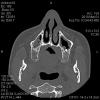

water10 Опубликовано 3 марта, 2010 Автор Поделиться Опубликовано 3 марта, 2010 Это срезы для лора, сейчас гайморит лечим. Вот этот еще симпатичнее и вполне информативный, у импланта форма трилистника. Ссылка на комментарий

Astronaft Опубликовано 3 марта, 2010 Поделиться Опубликовано 3 марта, 2010 Это срезы для лора, сейчас гайморит лечим. Вот этот еще симпатичнее и вполне информативный, у импланта форма трилистника.Диагноз "гайморит" не может быть поставлен по КТ.На КТ утолщение слизистой до 3-4мм. Это не патология само по себе и встречается у многих.Ничего аномального в имплантате стоящем на 1-3мм в пазуху нет. На сегодня это приемлемо в проф. кругах. Ссылка на комментарий

water10 Опубликовано 4 марта, 2010 Автор Поделиться Опубликовано 4 марта, 2010 а что за имплантат в форме трелистника? Уж не новокузнецкое ли это г-но?Очень интересно. Должен быть Xive, но имплант в пазуху я точно не покупала. Может пора и в марке засомневаться. Трилистник занимает 40% от общей высоты (по КТ). Ссылка на комментарий